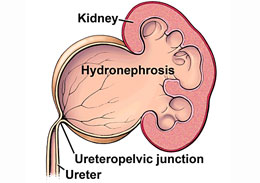

The ureteropelvic junction obstruction is an area where blockage occurs at the junction where bladder or ureter meets to the kidney. These blockage reduced flow of the urine down the ureter and increase of fluid pressure inside the kidneys. Generally the kidney makes filter and clean the blood and produce urine, then carries the waste items out of the body. The ureters are the tubes and carry urine from the kidneys for the bladder. When an ureteropelvic junction obstruction is present, the kidney becomes wide, which may lead to abatement in the kidney function over the time, the evolution of the kidney or urinary system, possibly and infections formation of kidney stones.